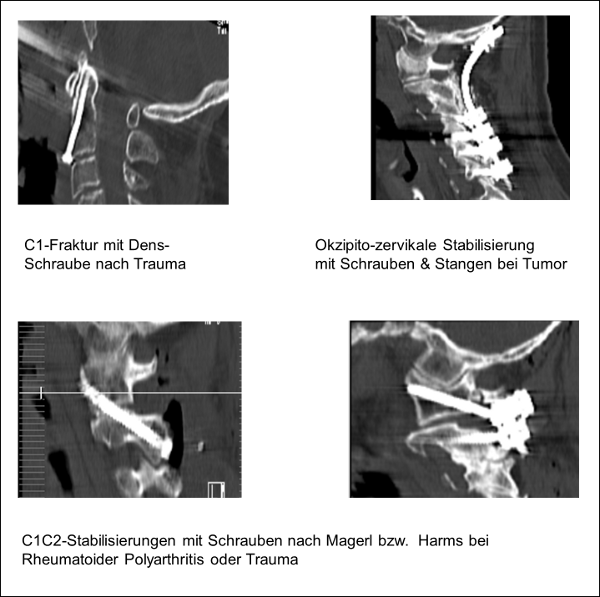

Die Behandlung kann konservativ oder chirurgisch erfolgen. Nach genauer diagnostischer Abklärung wird das am besten geeignete Verfahren angeboten. Oft besteht das chirurgische Behandlungsprinzip in einer Dekompression von Nervenstrukturen und einer gleichzeitigen Stabilisierung durch Metallstäbe und/ oder -schrauben.